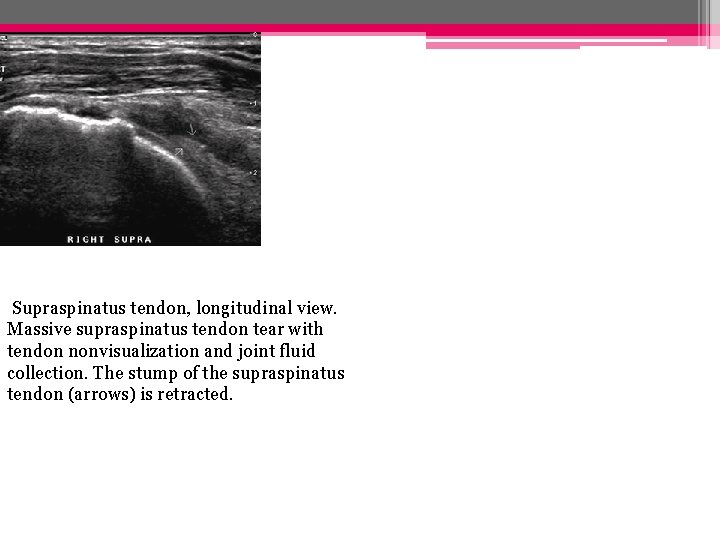

• Rupture complète: Rupture totale: important amincissement et perte de la convexité supérieure du tendon Rupture totale: désinsertion des fibres distales remplacées par du liquide )

Supraspinatus tendon, longitudinal view. Massive supraspinatus tendon tear with tendon nonvisualization and joint fluid collection. The stump of the supraspinatus tendon (arrows) is retracted.